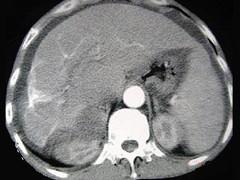

问题 男性,63岁,腹胀、双下肢浮肿、乏力、食欲不振,影像所见如下图,最佳的诊断是 ( )

选项 A.酒精性肝硬化 B.血吸虫肝硬化 C.肝炎后肝硬化 D.局限性脂肪肝 E.原发性肝癌

答案 B